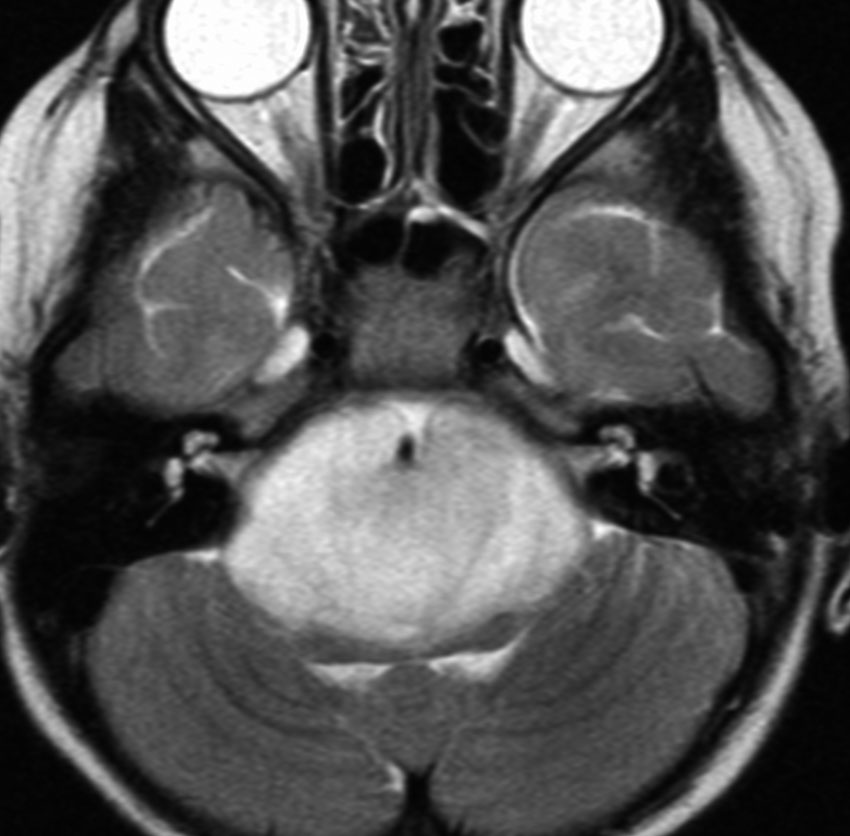

幼小児に発生するDIPG びまん性橋グリオーマです。ほとんどのびまん性正中グリオーマはDIPGです。脳幹部の橋の中央に発生し,橋が腫大します。